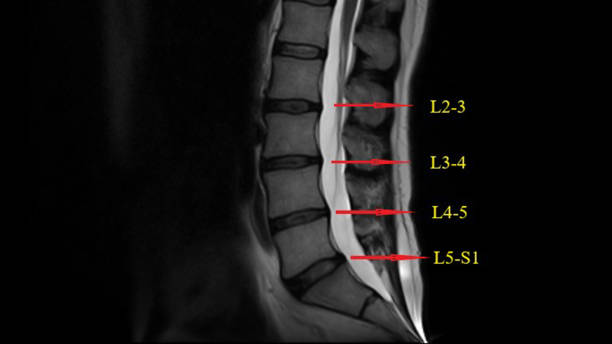

- MRI 검사: 허리 디스크의 손상 정도를 확인할 수 있습니다.